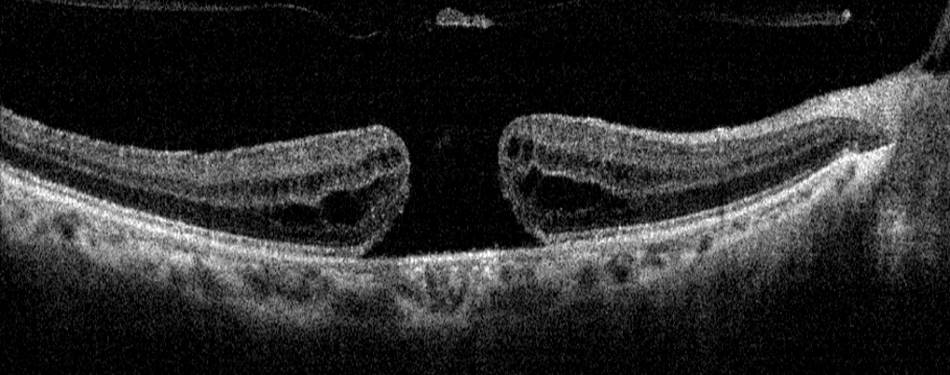

Macular Hole -:

Macula is the central part of the Retina, due to certain factors that is aeging changes, macular oedema or trauma there may develop a defect in thr central part called “Macular Hole”.

Diagnosis:- Retina Evaluation , OCT (Optical coherence tomography).

Treatment – Surgical treatment with Pars Plana Vitrectomy performed as early as possible.